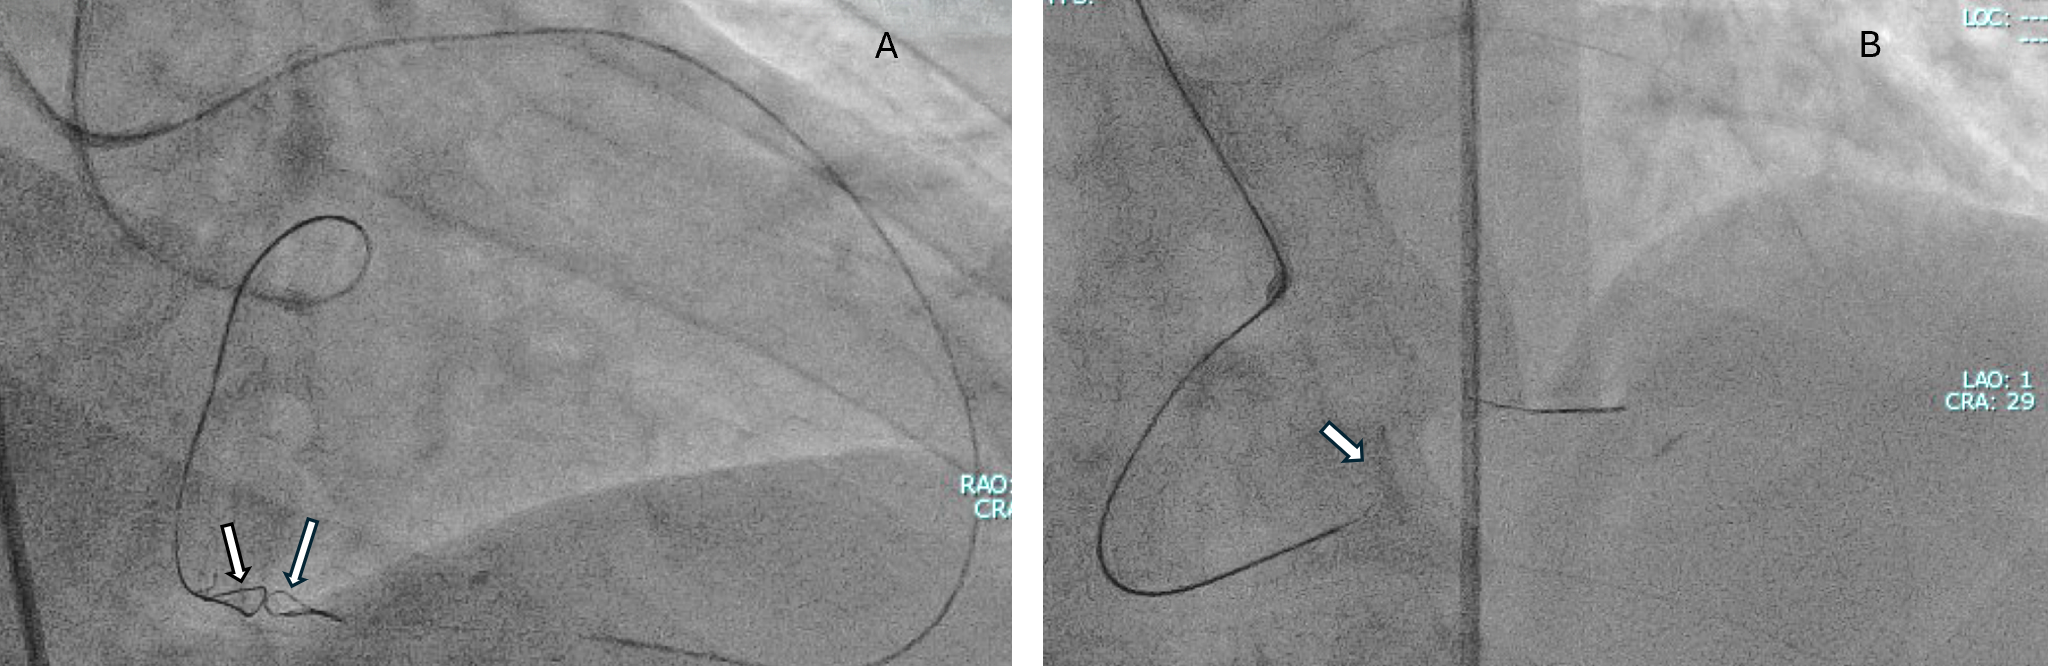

A 59-year-old man with exertional angina and coronary angiography showing chronic total occlusion (CTO) of the right coronary artery (RCA) with collateral filling from the left anterior descending artery (LAD) (Figure 1). Dual injection revealed an ambiguous proximal cap, a very long occlusion, and the distal cap at the bifurcation (Video 1).